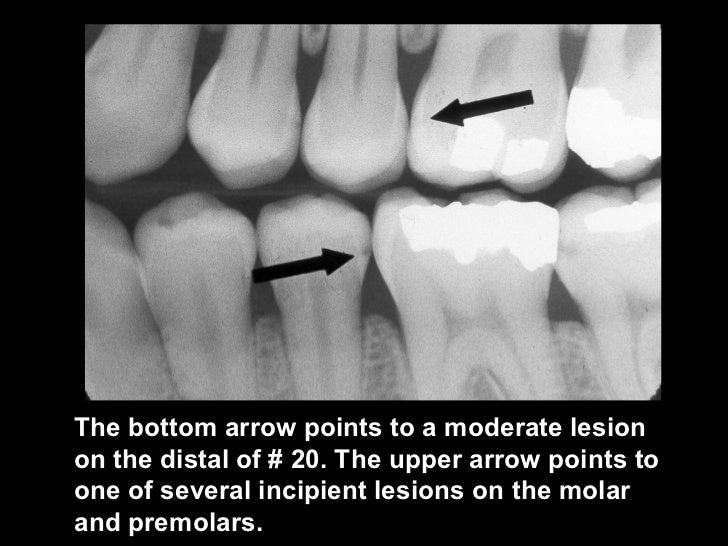

High Caries Risk Radiograph .   higher sensitivity is required for early detection of dental caries, such as in enamel.  conclusions caries detection determined by dental radiographs is highly accurate for proximal lesions and dentine caries lesions.   for detecting initial lesions, more sensitive methods could be considered in population with high caries risk and prevalence.  radiographic caries detection is especially suitable for detecting more advanced caries lesions, and has limited risks for false.   the caries risk profiling can aid the dentists in educating patients to reduce their sugar intake, increase fluoride.   radiographic caries detection is highly accurate for cavitated proximal lesions, and seems also suitable to detect dentine.   for a new patient visit, one or more of these disease indicators signals “high caries risk.” for a patient of record at a.